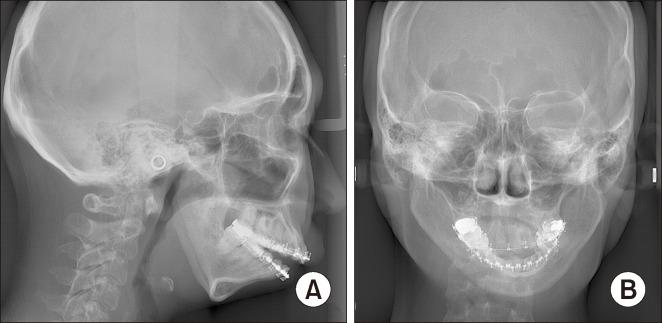

Untreated mandibular condyle fractures in childhood can result in significant jaw deformities, such as mandibular retrognathism, open bite, and facial asymmetry, which may necessitate surgical intervention in later years. Surgical approaches vary depending on the severity of the condition, including mandibular surgery alone, maxillomandibular surgery, or mandibular distraction osteogenesis (MDO). This report highlights a case involving mandibular retrognathism and open bite with condylar dislocation and malunion caused by untreated pediatric condyle fractures. Key challenges in this case included excessive anterior mandibular movement, irregular morphology of the mandibular ramus caused by malunion from fracture healing, and anteromedial dislocation of both condyles, all of which posed significant surgical complexities. The surgical approach combined Le Fort I osteotomy with MDO to perform maxillary impaction and mandibular advancement, followed by a secondary genioplasty. Notably, the dislocated temporomandibular joints were left untreated. Two years postoperatively, no relapse or recurrence of open bite was observed, and the dislocated condyles showed no positional and morphological changes, reflecting favorable outcomes. To our knowledge, this is the first reported case of orthognathic surgery combined with MDO for bilateral dislocated mandibular condyles, making it a valuable contribution to clinical practice.

儿童期未经治疗的下颌髁突骨折可导致严重的颌骨畸形,如下颌后缩、开颌和面部不对称,这可能在日后需要手术干预。手术方法因病情严重程度而异,包括单纯下颌手术、上颌下颌联合手术或下颌骨牵张成骨术(MDO)。本报告重点介绍了一例因儿童期髁突骨折未经治疗导致下颌后缩、开颌伴髁突脱位和骨不连的病例。该病例的主要挑战包括下颌前部过度移动、骨折愈合导致的骨不连引起的下颌升支形态不规则以及双侧髁突向前内侧脱位,所有这些都带来了重大的手术复杂性。手术方法结合了Le Fort I截骨术和MDO,以进行上颌骨上移和下颌骨前徙,随后进行二期颏成形术。值得注意的是,脱位的颞下颌关节未进行治疗。术后两年,未观察到开颌复发或再发,脱位的髁突也未出现位置和形态变化,显示出良好的效果。据我们所知,这是首例报道的正颌手术联合MDO治疗双侧脱位下颌髁突的病例,对临床实践具有重要价值。